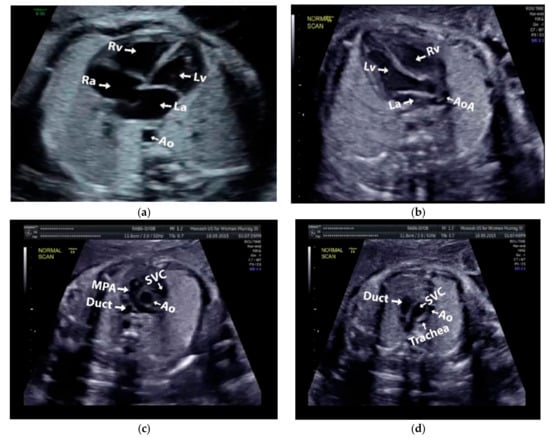

Images with inappropriate anatomical planes (cropped or badly captured) and those with calipers were excluded. The dataset composition was clearly imbalanced (some classes were more frequent than others), as is usually the case in real clinical scenarios. The sample of the raw ultrasound image was based on four views in normal anatomy, as depicted in Figure 2. In such sample, there are the left atrium (LA), left ventricle (LV), right atrium (RA), right ventricle (RV), ductus arteriosus (DUCT), superior vena cava (SVC), aorta ascendens (AoA), aorta descendens (Ao), and main pulmonary artery (MPA), whereas the sample of the raw ultrasound image of abnormal anatomy structure, with the three heart defects such as ASD, VSD, and AVSD condition, is compared to normal anatomy structure in Figure 3. In the abnormal structure, there are hole (H) as heart defect in each condition. Each defect has the variation of hole size; such hole size indicates the disease severity. However, in this study, we only detected the hole, without measuring the hole size.

Figure 2.

Fetal heart scan in four standard views of normal anatomy: (a) 4CH; (b) LVOT; (c) RVOT; and (d) 3VT.

The anatomical heart structures are critical for the segmentation process. The maternal–fetal clinician as the image annotator should drew precise boundaries around the heart images manually with data annotation tool (LabelMe) [7]. LabelMe to provide an online annotation tool to build image databases for computer vision research. The significant variations in image quality, shapes, sizes, and orientations between the pregnant women were used to create a database of ground truths. In the fetal echocardiography with normal anatomy, each standard view has a different structure of heart chamber; therefore, the annotation should be conduct for all standard views with their respective chamber such as, 4CH standard view consists of five heart chambers, i.e., Ao, LA, LV, RA, and RV; 3VT standard view consists of three heart chambers, i.e., DUCT, SVC, and AoA; LVOT standard view consists of five heart chambers, i.e., AoA, LA, LV, RA, and RV; and RVOT standard view consists of four heart chambers, i.e., DUCT, SVC, AoA, and MPA.

3.1. Fetal Heart Standard View Segmentation

We benchmarked widely used state-of-the-art CNNs-based Mask-RCNNs with three different backbone architectures: ResNet50, ResNet101, and MobileNetV1. The networks’ original architecture of Mask-RCNN was maintained in all cases. All networks were first pre-trained using the Microsoft common objects in context (COCO) dataset, then fully retrained using our training data to produce the probability scores for each class. We conduct the fetal heart standard view segmentation with normal anatomy of the 4CH view, the expected normal appearance of the LVOT/RVOT view and the additional views required for the complex ultrasound obstetric images with 3VT view. Whereas fetal heart abnormality anatomy examination by using only the 4CH view.

Generally, maternal–fetal clinicians use their judgement to determine whether certain heart substructures are in the correct anatomical localizations by comparing normal and abnormal fetal heart images. Four standard views in the ultrasound images are used in examinations to perform fetal heart diagnoses. In this study, the fetal heart view was segmented automatically using the proposed model. Fetal heart chamber as an object should be detected and segmented in the four fetal heart standard views namely, AoA, AoD, LA, RA, LV, RV, DUCT, SVC, and MPA. Figure 8 and Figure 9 presented the heart chamber prediction performance for a standard fetal heart scan in terms of the IoU and DCS (Jaccard index) performance. A total of 17 heart chambers are needed to be segmented and detected: five objects for 4CH view, three objects for 3VT view, five objects for LVOT view, and four objects for RVOT view.